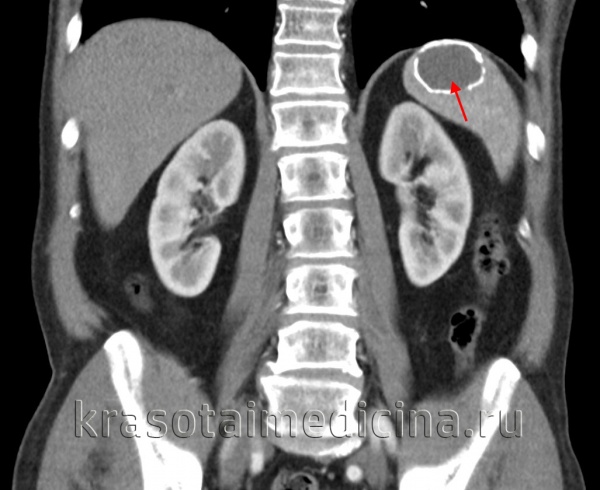

о Единичная однокамерная киста с плотностью, близкой к плотности воды, и четкими контурами:

- Имеет тонкую стенку, четко отграничена от неизмененной ткани селезенки

- В кисте отсутствует солидный компонент (узлы), участки накопления контраста внутри или на периферии кисты

- Всегда расположены внутри паренхимы селезенки и не обладают экзофитным характером роста

о В кистах могут обнаруживаться обызвествления в виде «яичной скорлупы» либо широкие кальцинаты по периферии

• Врожденные и приобретенные кисты могут быть неотличимы друг от друга:

о Врожденные кисты: обычно простые

о Приобретенные: чаще сложные, содержат обызвествления